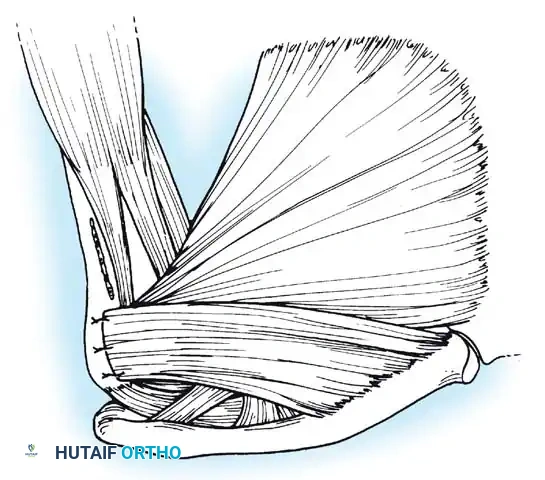

Subscapularis Management

Exposure of the anterior capsule requires navigating the subscapularis muscle. Historically, a vertical tenotomy was performed; however, modern techniques favor a subscapularis split or a peel to preserve the integrity of the muscle belly and its tendinous insertion.

- The Split: A horizontal split is made in the subscapularis at the junction of its middle and inferior thirds, extending from the lesser tuberosity medially.

- Separation: The subscapularis is carefully elevated off the underlying anterior joint capsule. This plane can be scarred in revision cases, requiring meticulous sharp dissection to avoid inadvertent capsulotomy.